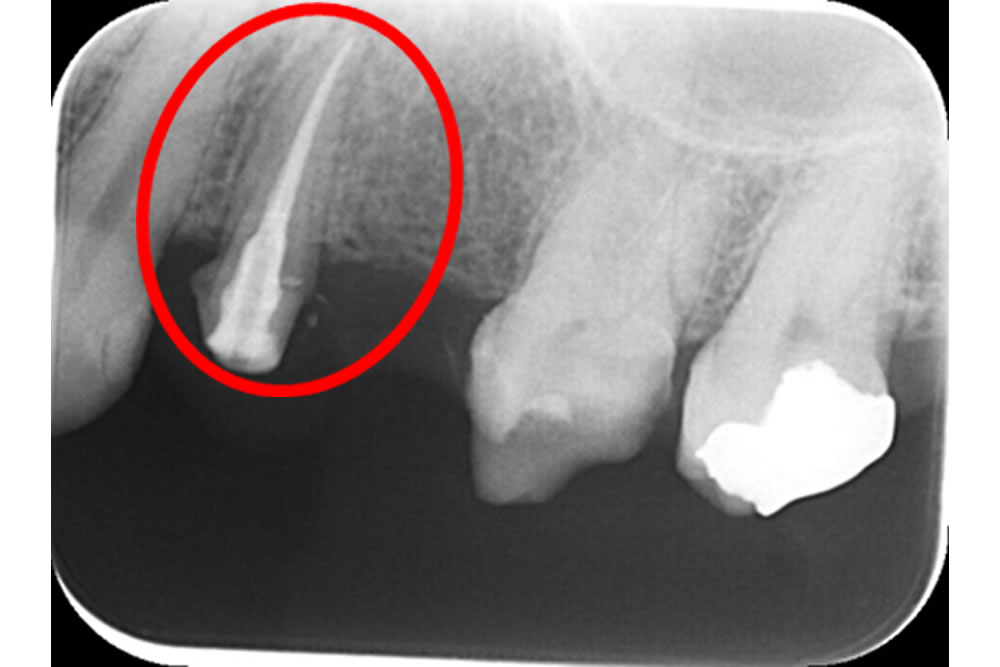

こちらの患者さまは他院で入れたブリッジの土台の歯(4番目の歯)の歯茎が腫れてきてしまったため、治療を行うことになりました。

根の治療を終え、最終的なお薬を詰めました。その後、痛みなど症状がないことを確認し、4番目の歯に土台を立て、再度4.5.6番目をかけるブリッジの型どりを進めていきます。